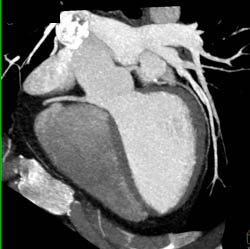

Metastatic Melanoma Invades the Left Atrium Via the Right Pulmonary Vein